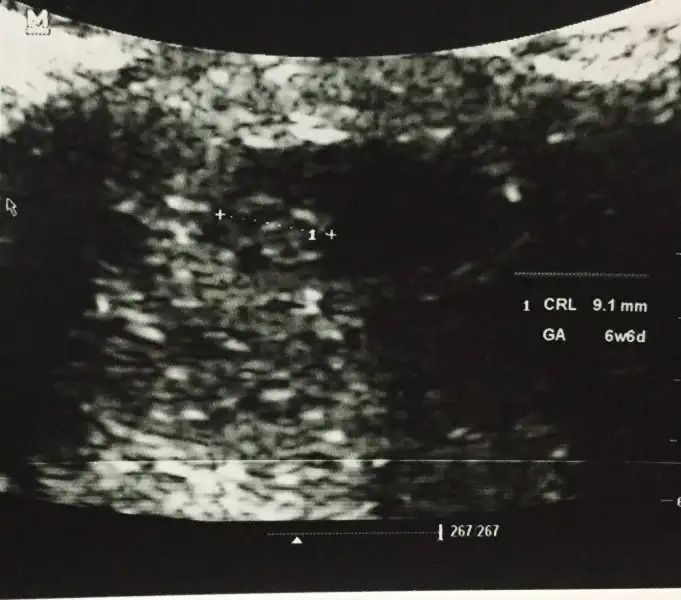

Teoriye gore erkekBenim de 6+6 ilk görüntüm var hadi arkadaşlar yorumlarınızı bekliyorum kız mı erkek mi